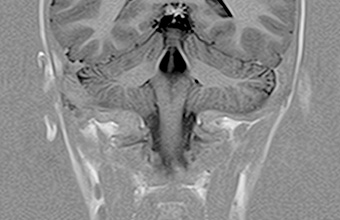

Neurološka snimanja

Neurološka MR snimanja glave i kralježnice istražuju od mogućih tumora mozga do hernijacija diska kralježnice visoko kvalitetnim morfološkim i funkcionalnom tehnikama.